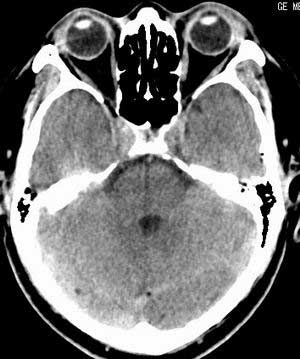

患者男,58岁。耳爆震伤后耳聋2年余,而后双耳道肿胀,间断性流脓。近一月来头痛、恶心、呕吐,右眼红痛,不能入眠。

在平扫时,见右侧枕骨下方小脑半球表面带状模糊稍高密度影,考虑为耳源性脑内感染。

平扫右侧岩骨与枕骨交角内侧脑质内见淡片状密度增高影,内缘清晰。增强图象上未见明显显示。

右枕颅骨内板下高密度应该是窦的变异,和其症状应该无关,根据病史另找原因吧。[em16]

条状高密度为小脑幕吧

条状高密度为小脑幕

横窦乙状窦。

增强的横窦乙状窦。